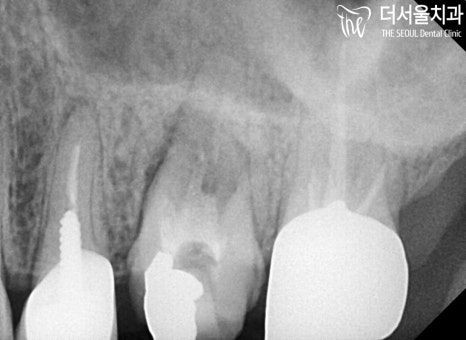

지르코니아 크라운이 제작되기 전까지

임시치아를 씌워 이를 살리도록 하되,

이후 제작이 되었을때 세팅을 해드리는 것으로

진료는 끝마쳤는데요.

처음에 보였던 잇몸 물집

깔끔히 제거된 것을 볼 수 있죠?

수포가 없어져 환자분 또한

마음이 놓인다며,